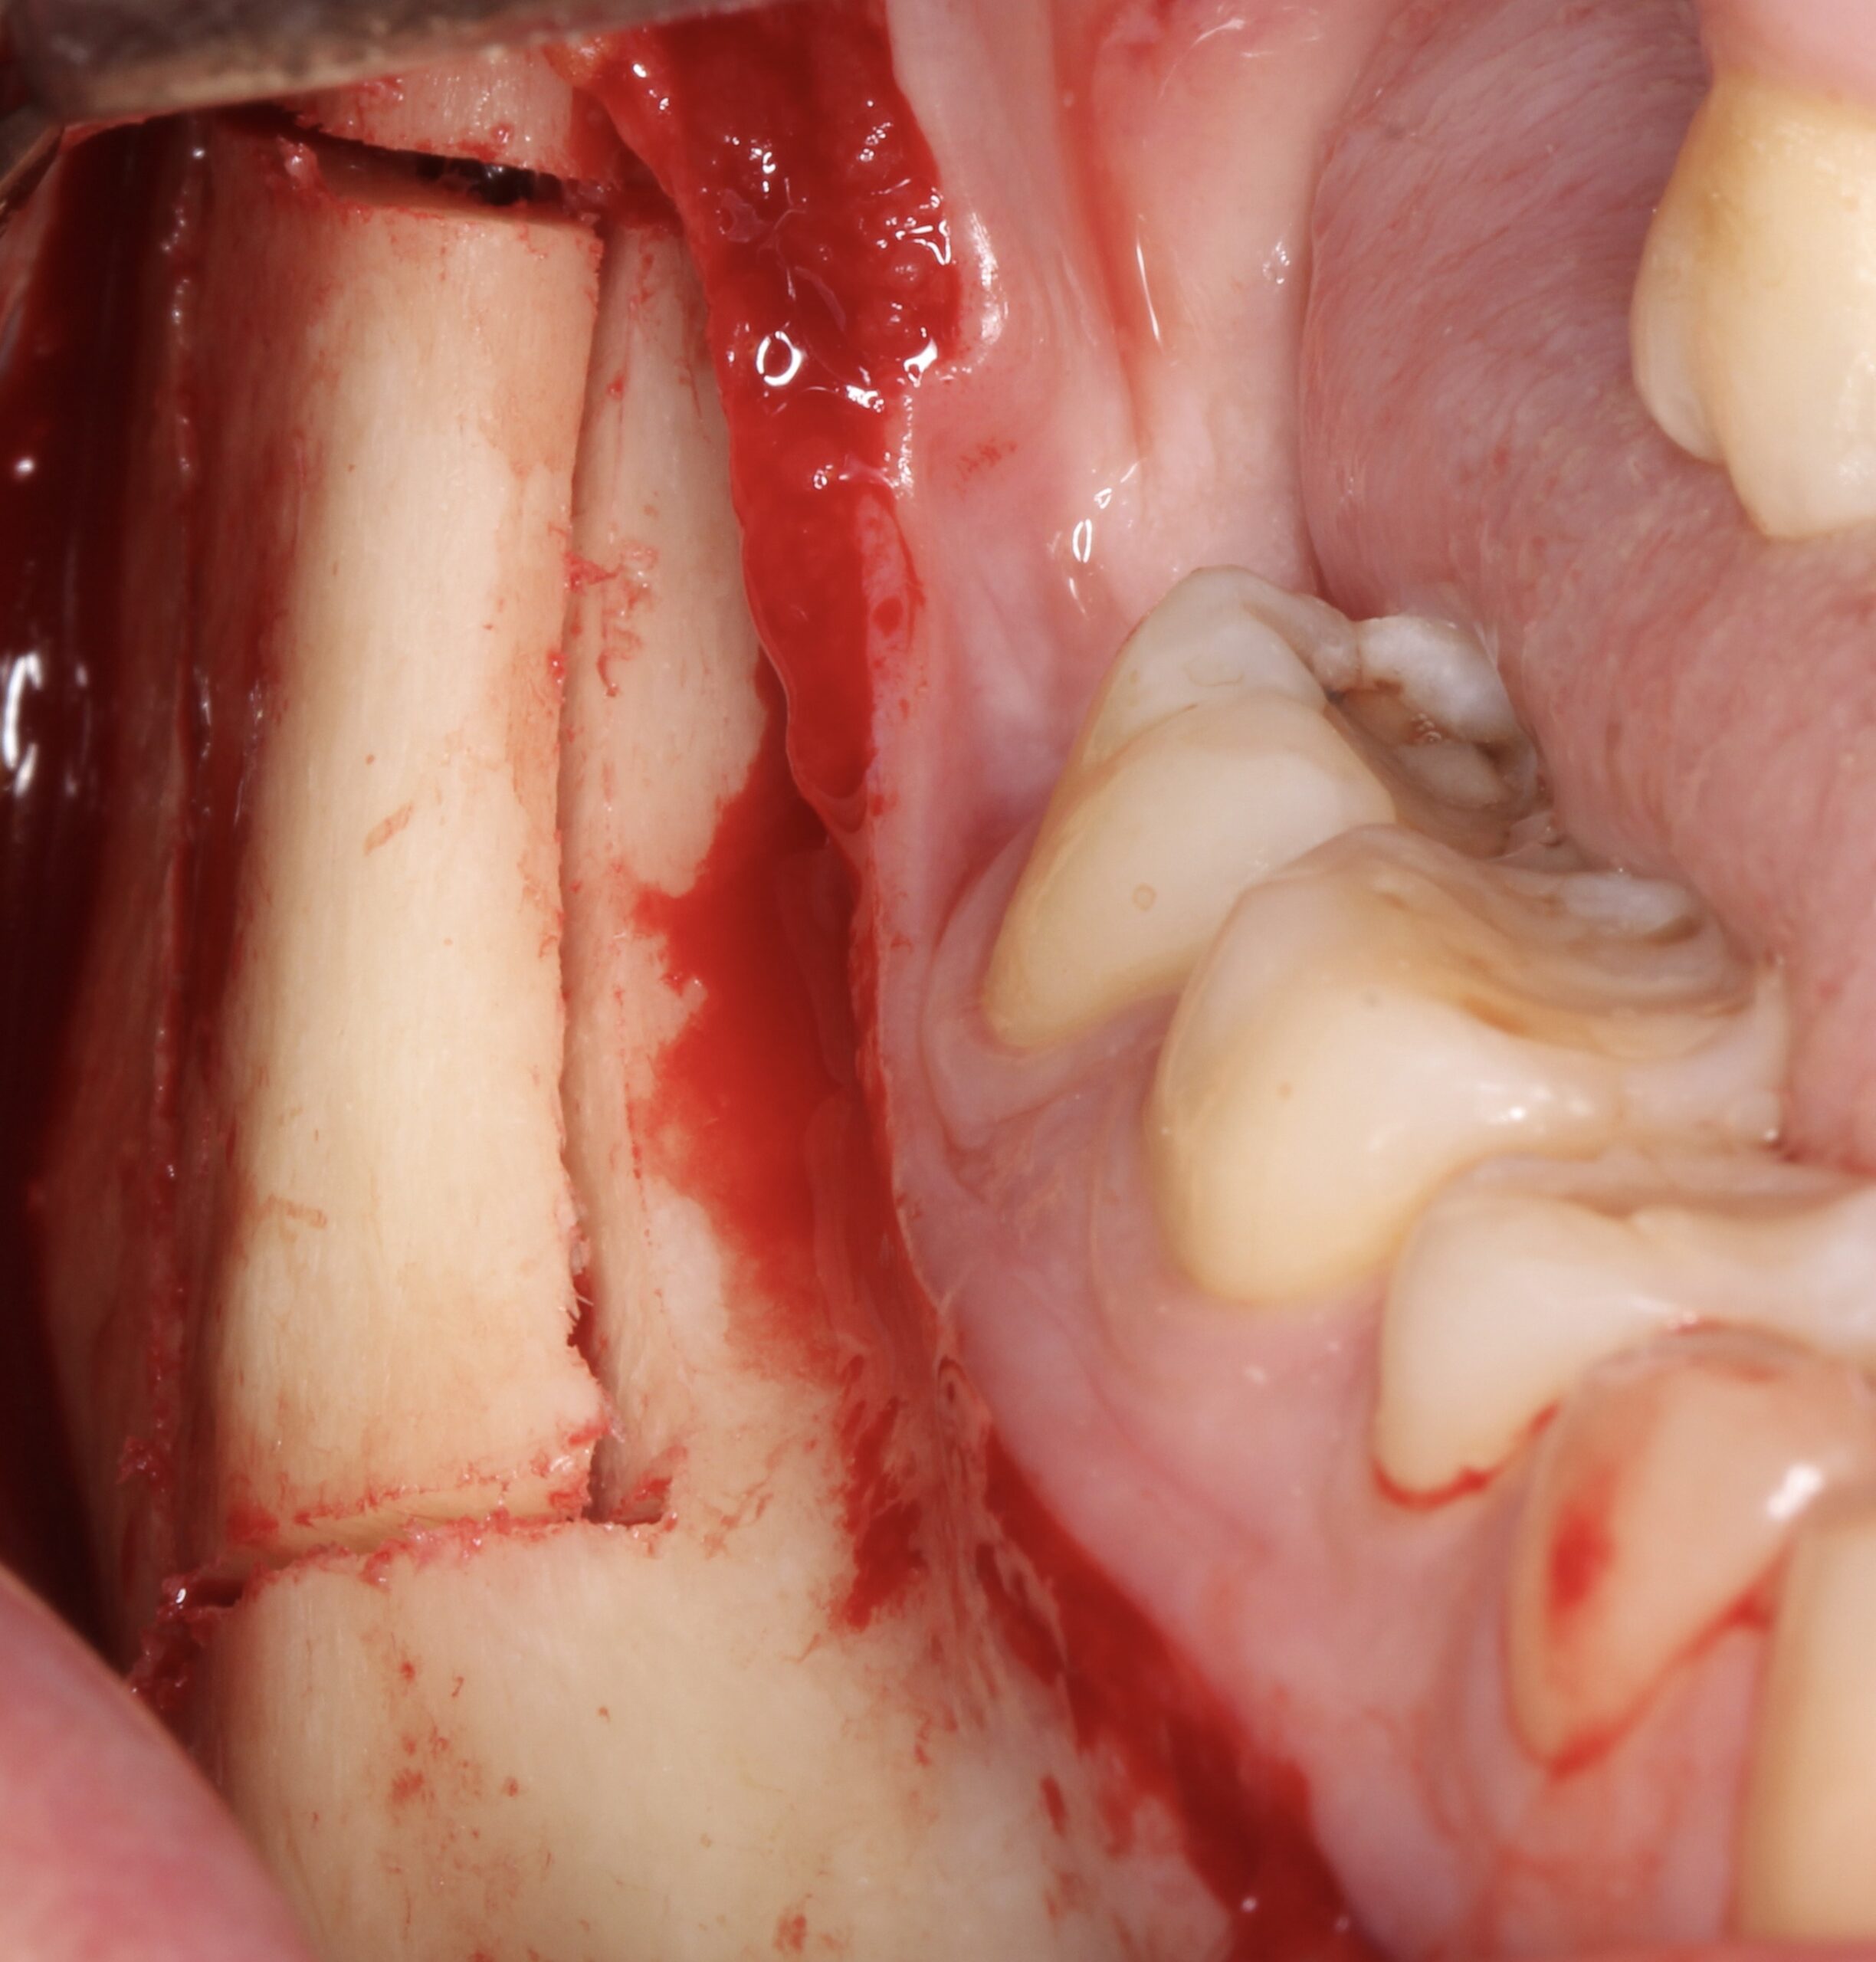

Figure 3.

Block at the resorbed left posterior maxilla before raising the flap.

Figure 4.

After raising the flap a 9 mm vertical defect was found.